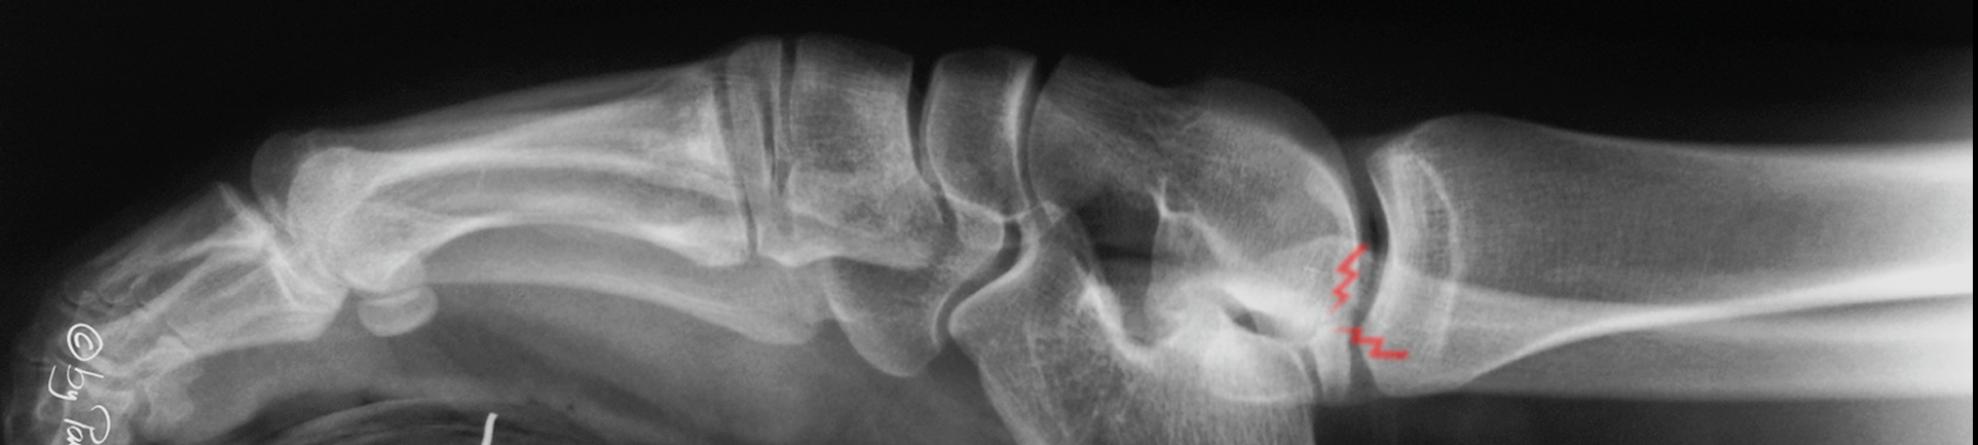

Osteochondral fracture?

45 year old male. ankle inversion injury 3 days ago